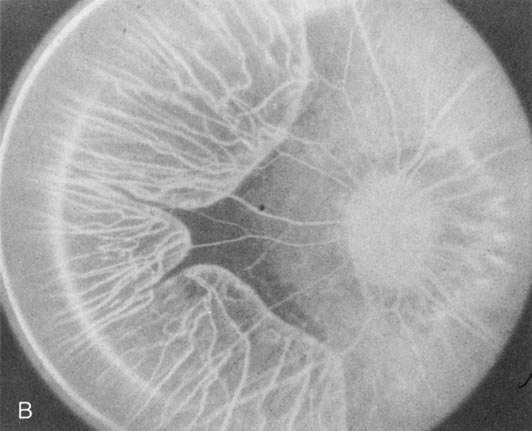

Fig. 1. Retinitis pigmentosa. A. A typical area of bone spicule pigmentation. B. Diffuse dye leakage is apparent throughout the posterior pole. C. The early angiogram shows dilated and irregular retinal radial peripapillary capillaries and perifoveal retinal capillaries. D. Leakage from these vessels are evident in the late angiogram.

Dye leakage in RP may occur from the retinal vessels or at the level of the retinal pigment epithelium (Fig. 1B).2–4 The leakage may be seen in the macula and posterior pole, along the vascular arcades in the distribution of the radial peripapillary capillaries, and in the periphery (where an exudative vasculopathy resembling Coats' disease is suggested).

Of more clinical importance is the role of FA in the diagnosis and treatment of cystoid macular edema (CME) (Fig. 1C and D). Stereoscopic FA indicates that the leakage, which may be diffuse or have the typical petaloid stellate appearance of CME, can come from the perifoveal retinal capillaries, from the choroid through the RPE, or from a combination of both sources.4 With the recent suggestion that CME in RP may be successfully treated with acetazolamide,5, 6 FA is thus important to document the diagnosis of CME, establish the origin(s) of leakage, and follow patients during and after therapy.